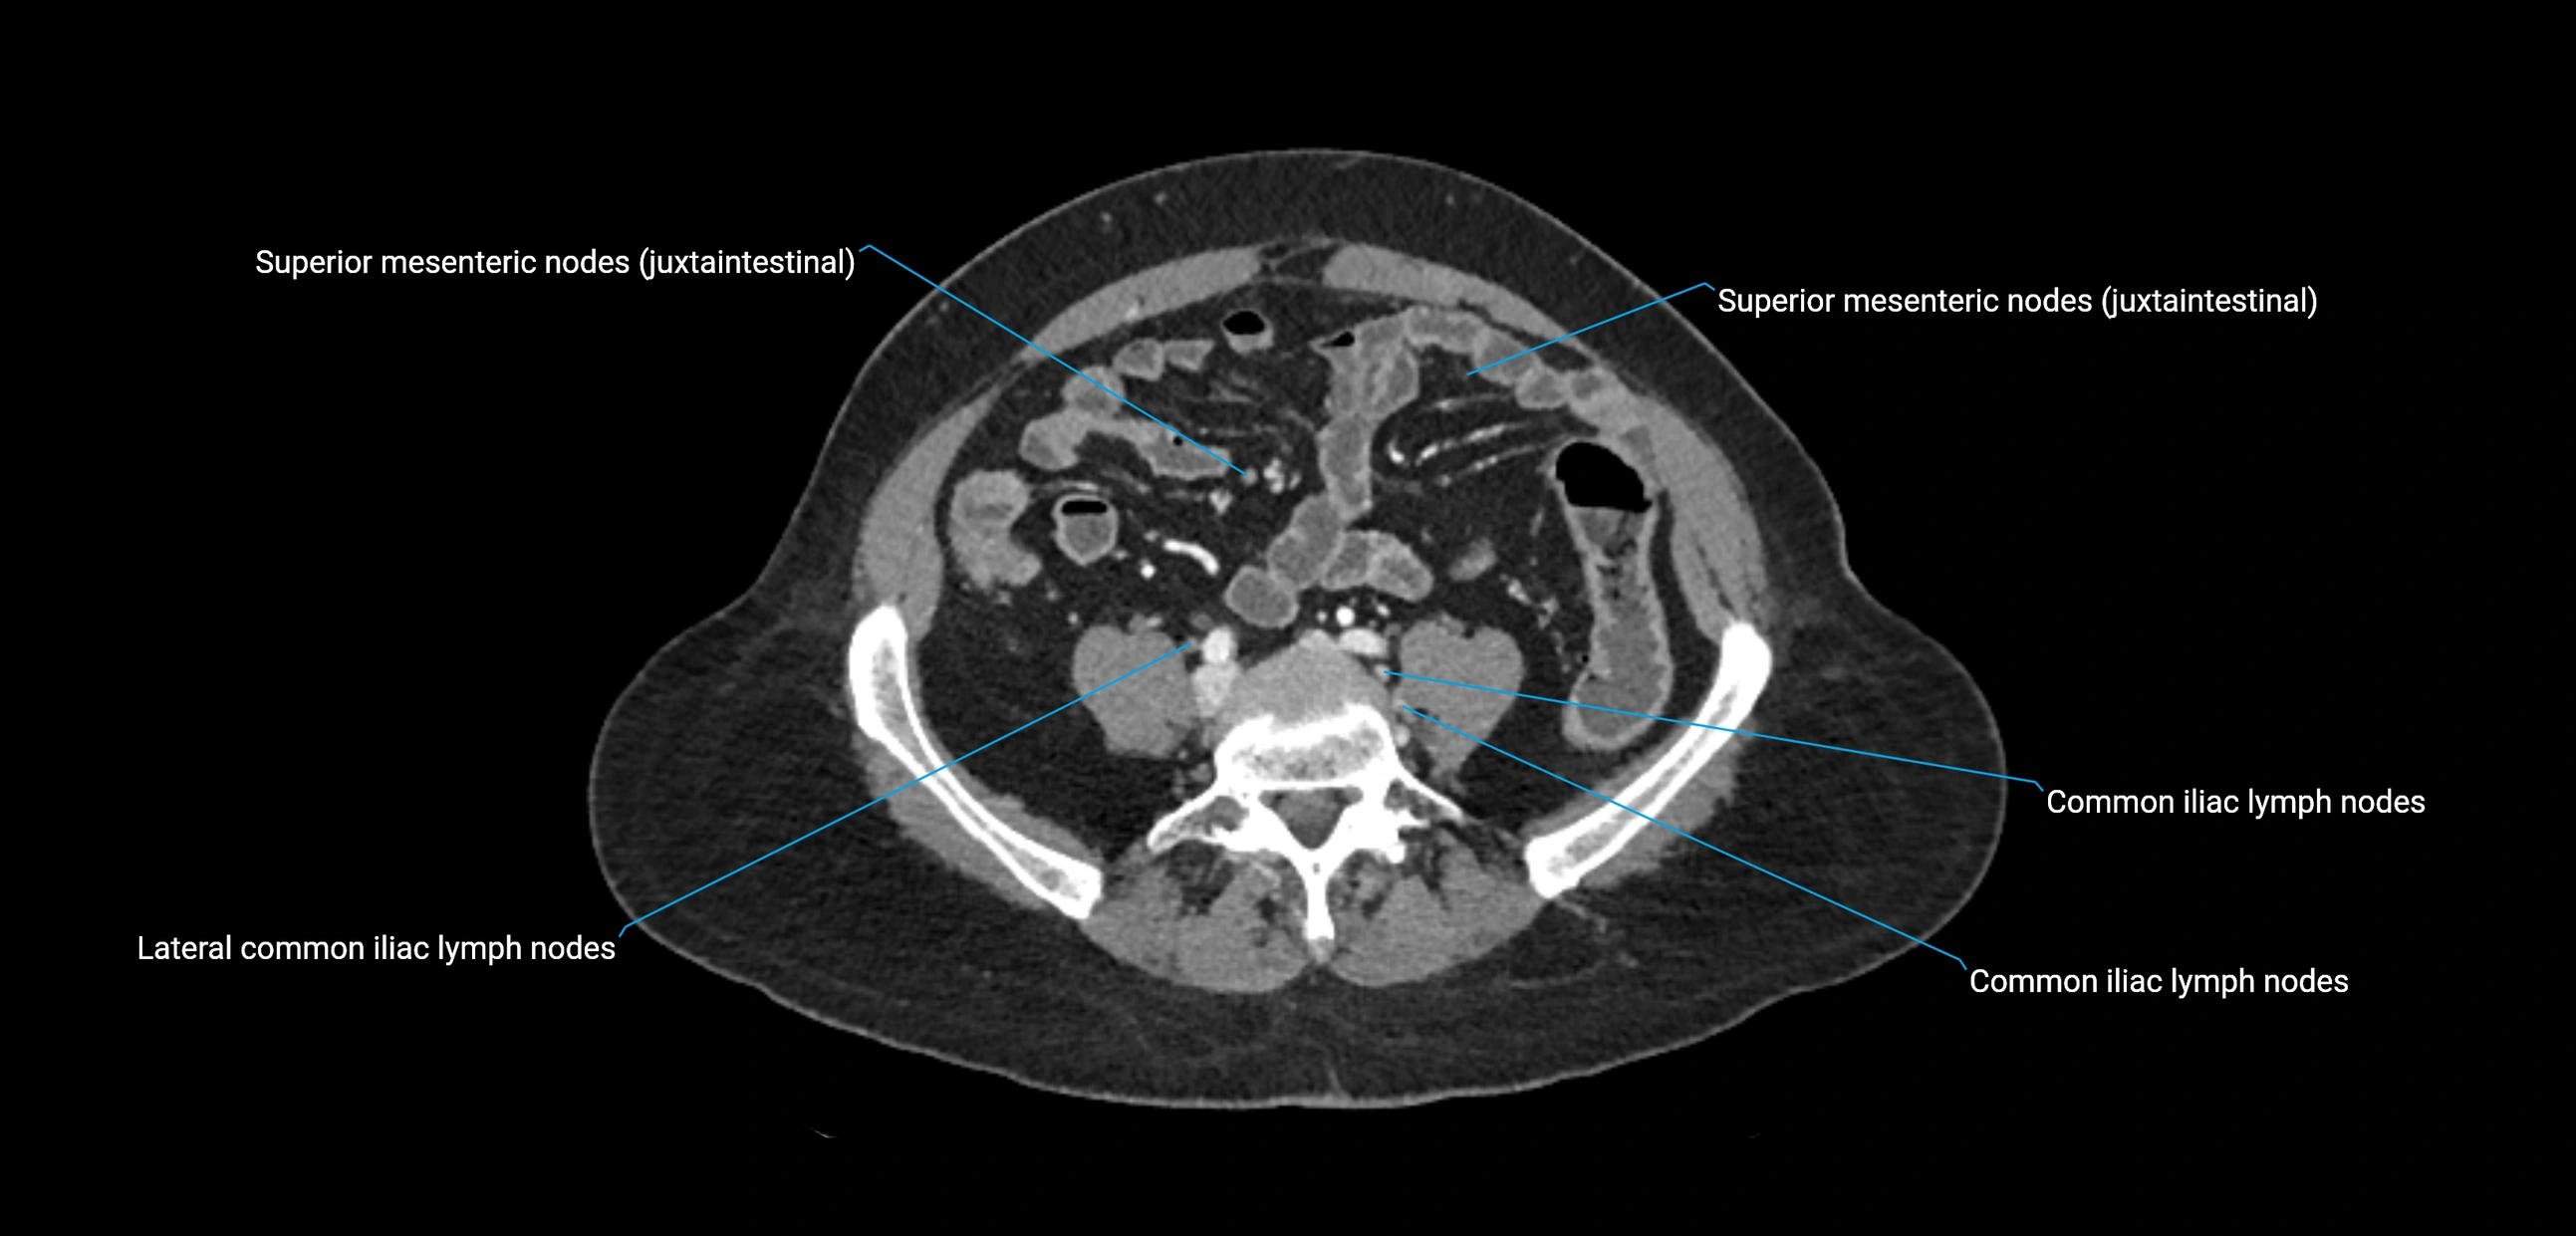

CT Appearance

CT Pre-Contrast:

• Nodes appear as soft-tissue density nodules adjacent to the aorta and IVC

• Calcification may be seen in chronic infections (e.g., tuberculosis)

CT Post-Contrast:

• Normal nodes enhance homogeneously

• Malignant nodes may show heterogeneous enhancement, central necrosis, or conglomerate formation

• Size >1 cm short axis is suspicious, though morphology and distribution are equally important